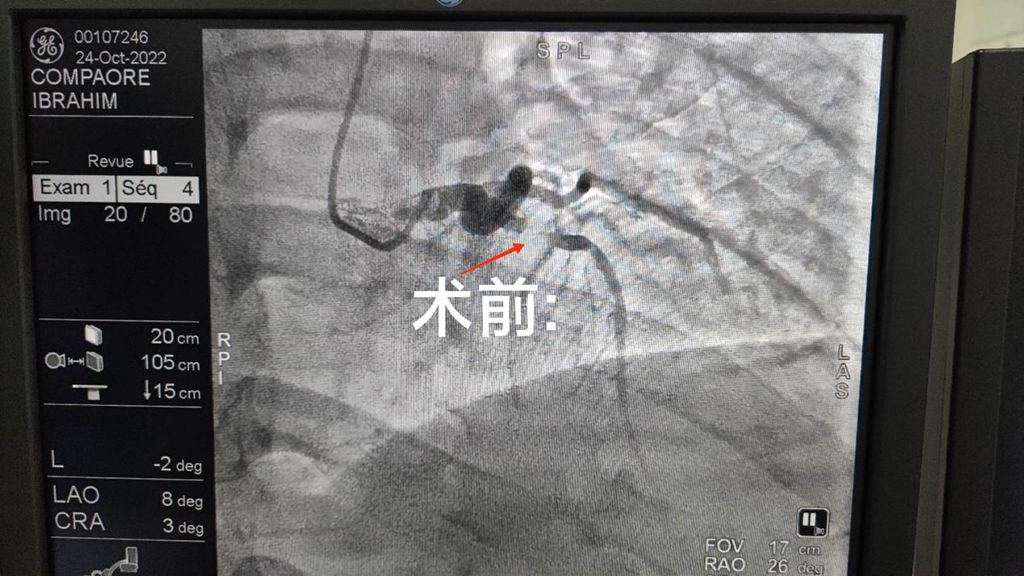

新一批队员到来之后,我很快融入集体,继续开展工作,运用自己的专业知识服务当地患者。由于当地气候等多方面原因,用于手术的DSA机器出现故障,历经重重困难,于近日维修完毕后,立即投入临床工作。最近在门诊接诊两名患者,都因间断胸前区疼痛,胸闷,来院就诊;结合患者心电图及临床症状,考虑冠心病可能;在权衡手术治疗和药物保守疗法的风险和利弊以后,建议患者行冠脉造影检查,安排患者住院治疗。其中一位患者行冠状动脉造影检查:提示前降支重度狭窄,给予前降支植入一枚支架,和当地医生一起完成手术:手术过程中,由于语言的差异,有时会用上“肢体语言”,用手比划。大家克服困难,齐心协力,共同完成手术。